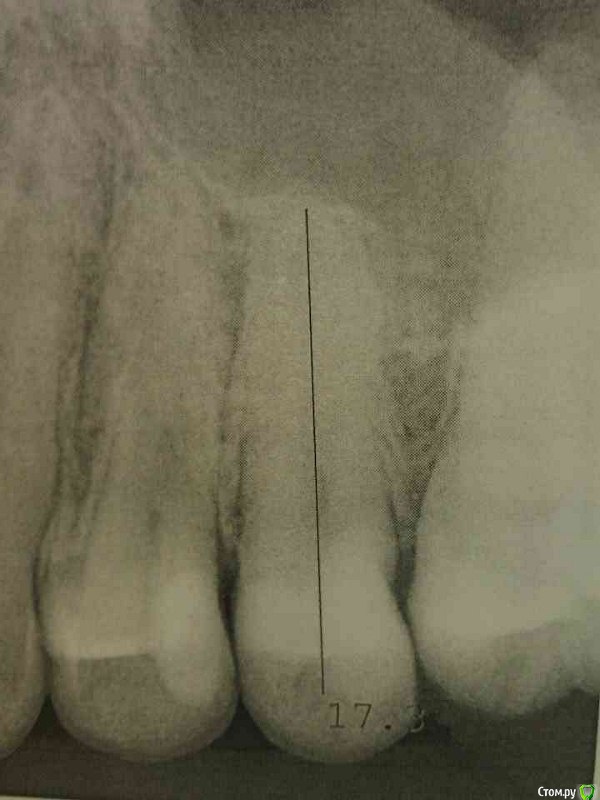

2. Во воторой клинике, также был сделан снимок (снимок как раз приложен), врач пулипита не увидел но сказал что пломба большая, близко к пулье и также нужно депульпировать зуб. :(

снимок не особо информативен

то, что Вы описываете может быть проявлением периодонтита, а возможно произошло "отделение" пломбы от зуба

необохимо произвести тест на витальность зуба и решать вопрос о депульпации